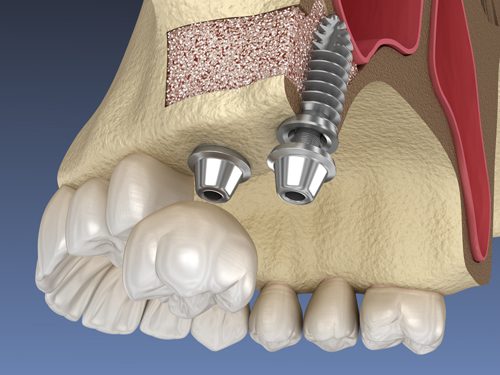

Existen casos en los que inicialmente no se pueden colocar implantes porque no hay hueso suficiente. Para estos casos es necesario aumentar la altura o la anchura del hueso existente para su colocación.

En la Clínica Dental ECCO aplicamos técnicas quirúrgicas de regeneración ósea previa a la colocación de los implantes: injertos óseos, obtención de plasma rico en factores de crecimiento, preservación alveolar y elevación de senos maxilares.

infografía explicativa de refeneración ósea